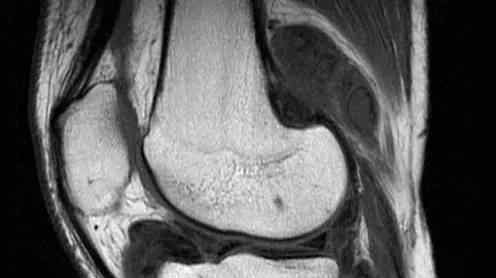

弹跳低、钝、频,来自骨外侧的髌股关节,伴有关节肿胀,偶有联锁征象。MRI显示关节退变,半月板呈“孤立岛状”。关节镜下可见关节软骨和半月板退变,韧带和关节囊骨质增生和受压。

(1)外伤所致半月板损伤:声音清脆,频率高,关节间隙压痛,交锁。核磁共振可以做出明确的诊断。关节镜下可见半月板破裂,可嵌入胫股关节形成交锁。

(2)首先赋予盘状半月板。从小就经常蹦蹦跳跳,多见于膝盖外侧,清脆,频率高。如果是劈开,可以形成膝关节互锁。x线能显示关节间隙较宽,MRI能明确诊断。关节镜下可以看到半月板呈盘状,如果有疼痛和悲哀,可以看到裂开或折叠。

(3)半月板囊肿是由性别或外伤形成的。频率低,声音低沉生硬,有一种不典型的互锁。如果囊肿是囊肿,可以在膝眼处向外膨出。MRI可显示与半月板密切相关的囊肿。关节镜下可看到半月板边缘的包膜,半月板偶有损伤。

外伤造成的。膝关节不稳定导致弹跳,频率低且钝,可能伴有互锁。抽屉测试呈阳性。核磁共振可以明确诊断。关节镜下可见韧带断端嵌于关节间隙,或有软骨损伤。